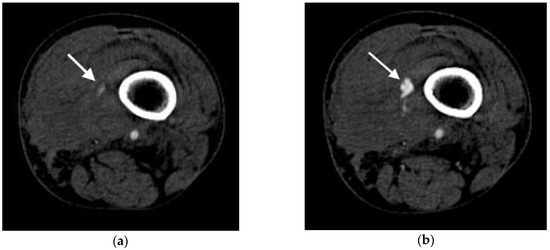

2.4.1. Active Arterial Extravasation